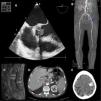

A 64-year-old man with ulcerative colitis was admitted to hospital for 2 weeks of high temperature and tiredness. One month before admission he had undergone aortic valve replacement surgery (PERIMOUNT bioprosthesis, Edwards Lifesciences, United States). Infective endocarditis (IE) was suspected and large vegetation on aortic prosthesis valve was seen. In his fifth day of admission, he rapidly progressed to cardiogenic shock due to left-outflow tract obstruction (Fig. 1A), requiring emergent surgery. Blood cultures were negative. As soon as the explanted prosthetic valve culture showed Aspergillus flavus Voriconazole and Micafungin were initiated. Despite early surgery and antifungal therapy, he had an early relapse of IE. During this second episode, he developed multiple embolisms: right-common iliac artery thrombosis (Fig. 1B, red arrow), left femoral artery thrombosis (blue arrow), left popliteal artery thrombosis (green arrow), spondylodiscitis (Fig. 1C), and celiac trunk thrombosis (Fig. 1D). He also developed left parietal intracranial hemorrhage (Fig. 1E).

He underwent a third cardiac surgery (Aspergillus flavus was again isolated) and vascular intervention, but after a long hospitalization, he finally died.

This image depicts the clinical features of fungal endocarditis, a rare disease with poor prognosis, characterized by large bulky vegetations, recurrent embolisms, and periannular complications.